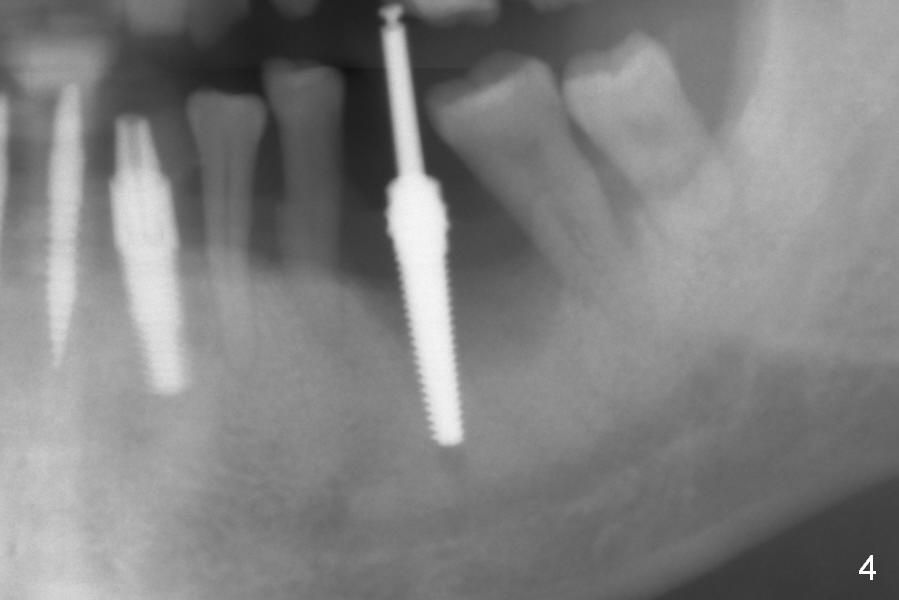

When the patient returns for #19 extraction and immediate implant, there is buccal (Fig.1 *) and lingual gingival swelling. The distobuccal root is exposed (D). Both the buccal and lingual walls are low. There is no septum. After removal of granulation tissue, an osteotomy is established in the bottom of the socket (slightly mesiolingually). The depth is approximately 3 mm in new bone (half of 6 mm and arrowhead). When the depth increases approximately 6 mm in new bone (Fig.3 arrowhead with 6x20 mm tap (T) in place), the Inferior Alveolar Canal is still invisible in PA. Panoramic X-ray has to be taken (Fig.4). So far infiltration anesthesia has been administered. When #2 sensor is inserted in the lingual vestibule, the patient feels pain and nausea. Lingual Nerve block is provided. The patient feels pain when further osteotomy is carried on. Since the depth of the osteotomy is confirmed by panoramic X-ray, Inferior Alveolar Nerve block is added. A 6x17 mm tissue-level implant is placed with clearance from the Inferior Alveolar Canal (Fig.5: red dashed line: the superior border of the Canal). Therefore, Lingual Nerve block allows lower placement of sensor so that the Inferior Alveolar Canal is detectable by PA.